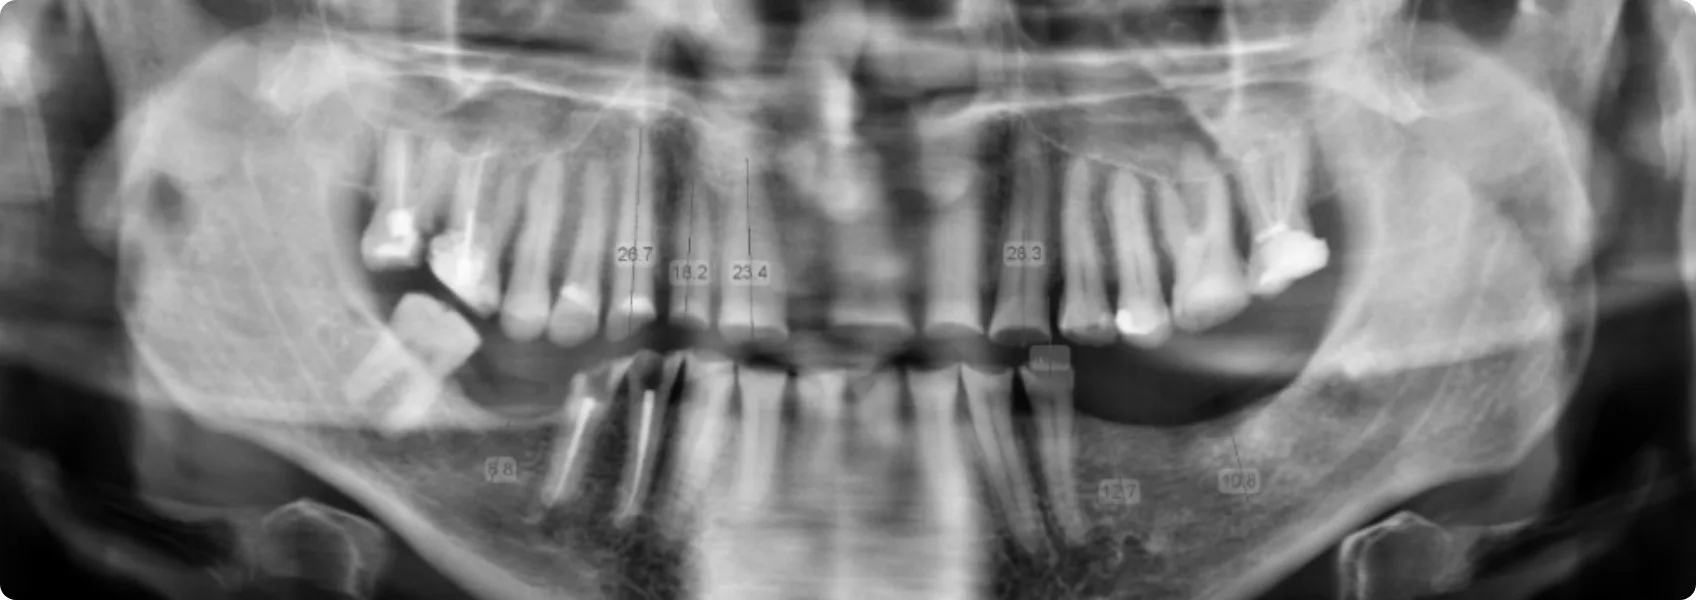

Najpierw dokładnie przeanalizowaliśmy i przygotowaliśmy fundamenty pod rekonstukcję. Zaczęliśmy od diagnostyki i analizy zdjęć RTG.

RTG pozwala zajrzeć „pod powierzchnię” – zobaczyć korzenie zębów, kość wyrostka zębodołowego, stan tkanek wokół korzeni, a także wewnętrzną budowę zębów (np. komorę miazgi, kanały korzeniowe).

Dzięki RTG możemy znaleźć stany zapalne, niewidoczne gołym okiem. Bez niego nie mielibyśmy jak wykryć problemów, które mogłyby prowadzić do poważnych powikłań.

RTG pokazało, że filary zębów własnych Pacjenta — te, na których miała opierać się przyszła rekonstrukcja — były zbyt krótkie.